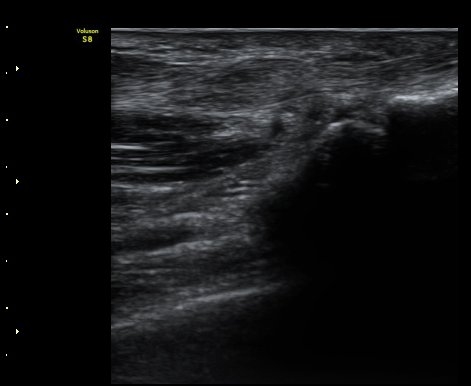

ÃÊÀ½ÆÄ °Ë»ç

ÈûÁÙÀÇ Á¾´Ü¸é°Ë»ç¿¡¼­ A1 ȰÂ÷(pulley)ÀÇ Àú¿¡ÄÚ ºÎÁ¾°ú ȰÀÚ ±ÙÀ§ºÎ¿¡¼­ ÈûÁÙÀÇ

ºÎÁ¾ÀÌ °üÂûµÊ(±×¸² 1, 2). ÈûÁ٠Ⱦ´Ü¸é°Ë»ç¿¡¼­ A1ȰÂ÷ÀÇ Àú¿¡ÄÚ ºÎÁ¾ÀÌ °üÃÔµÊ(±×¸² 3).